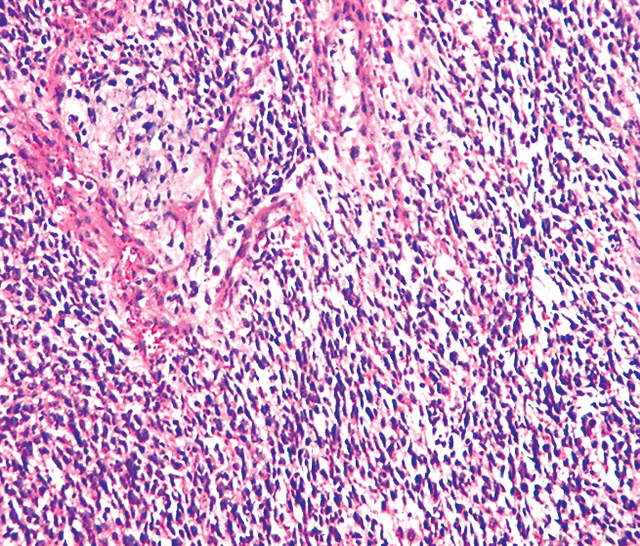

embryonal rhabdomyosarcoma cellularity appearances

embryonal rhabdomyosarcoma rms small cells tumor round hyperchromatic spindled typically ovoid

Rhabdomyosarcoma (orbit). Rhabdomyosarcoma pathophysiology. Orbit rhabdomyosarcoma embryonal webpathology rms comments